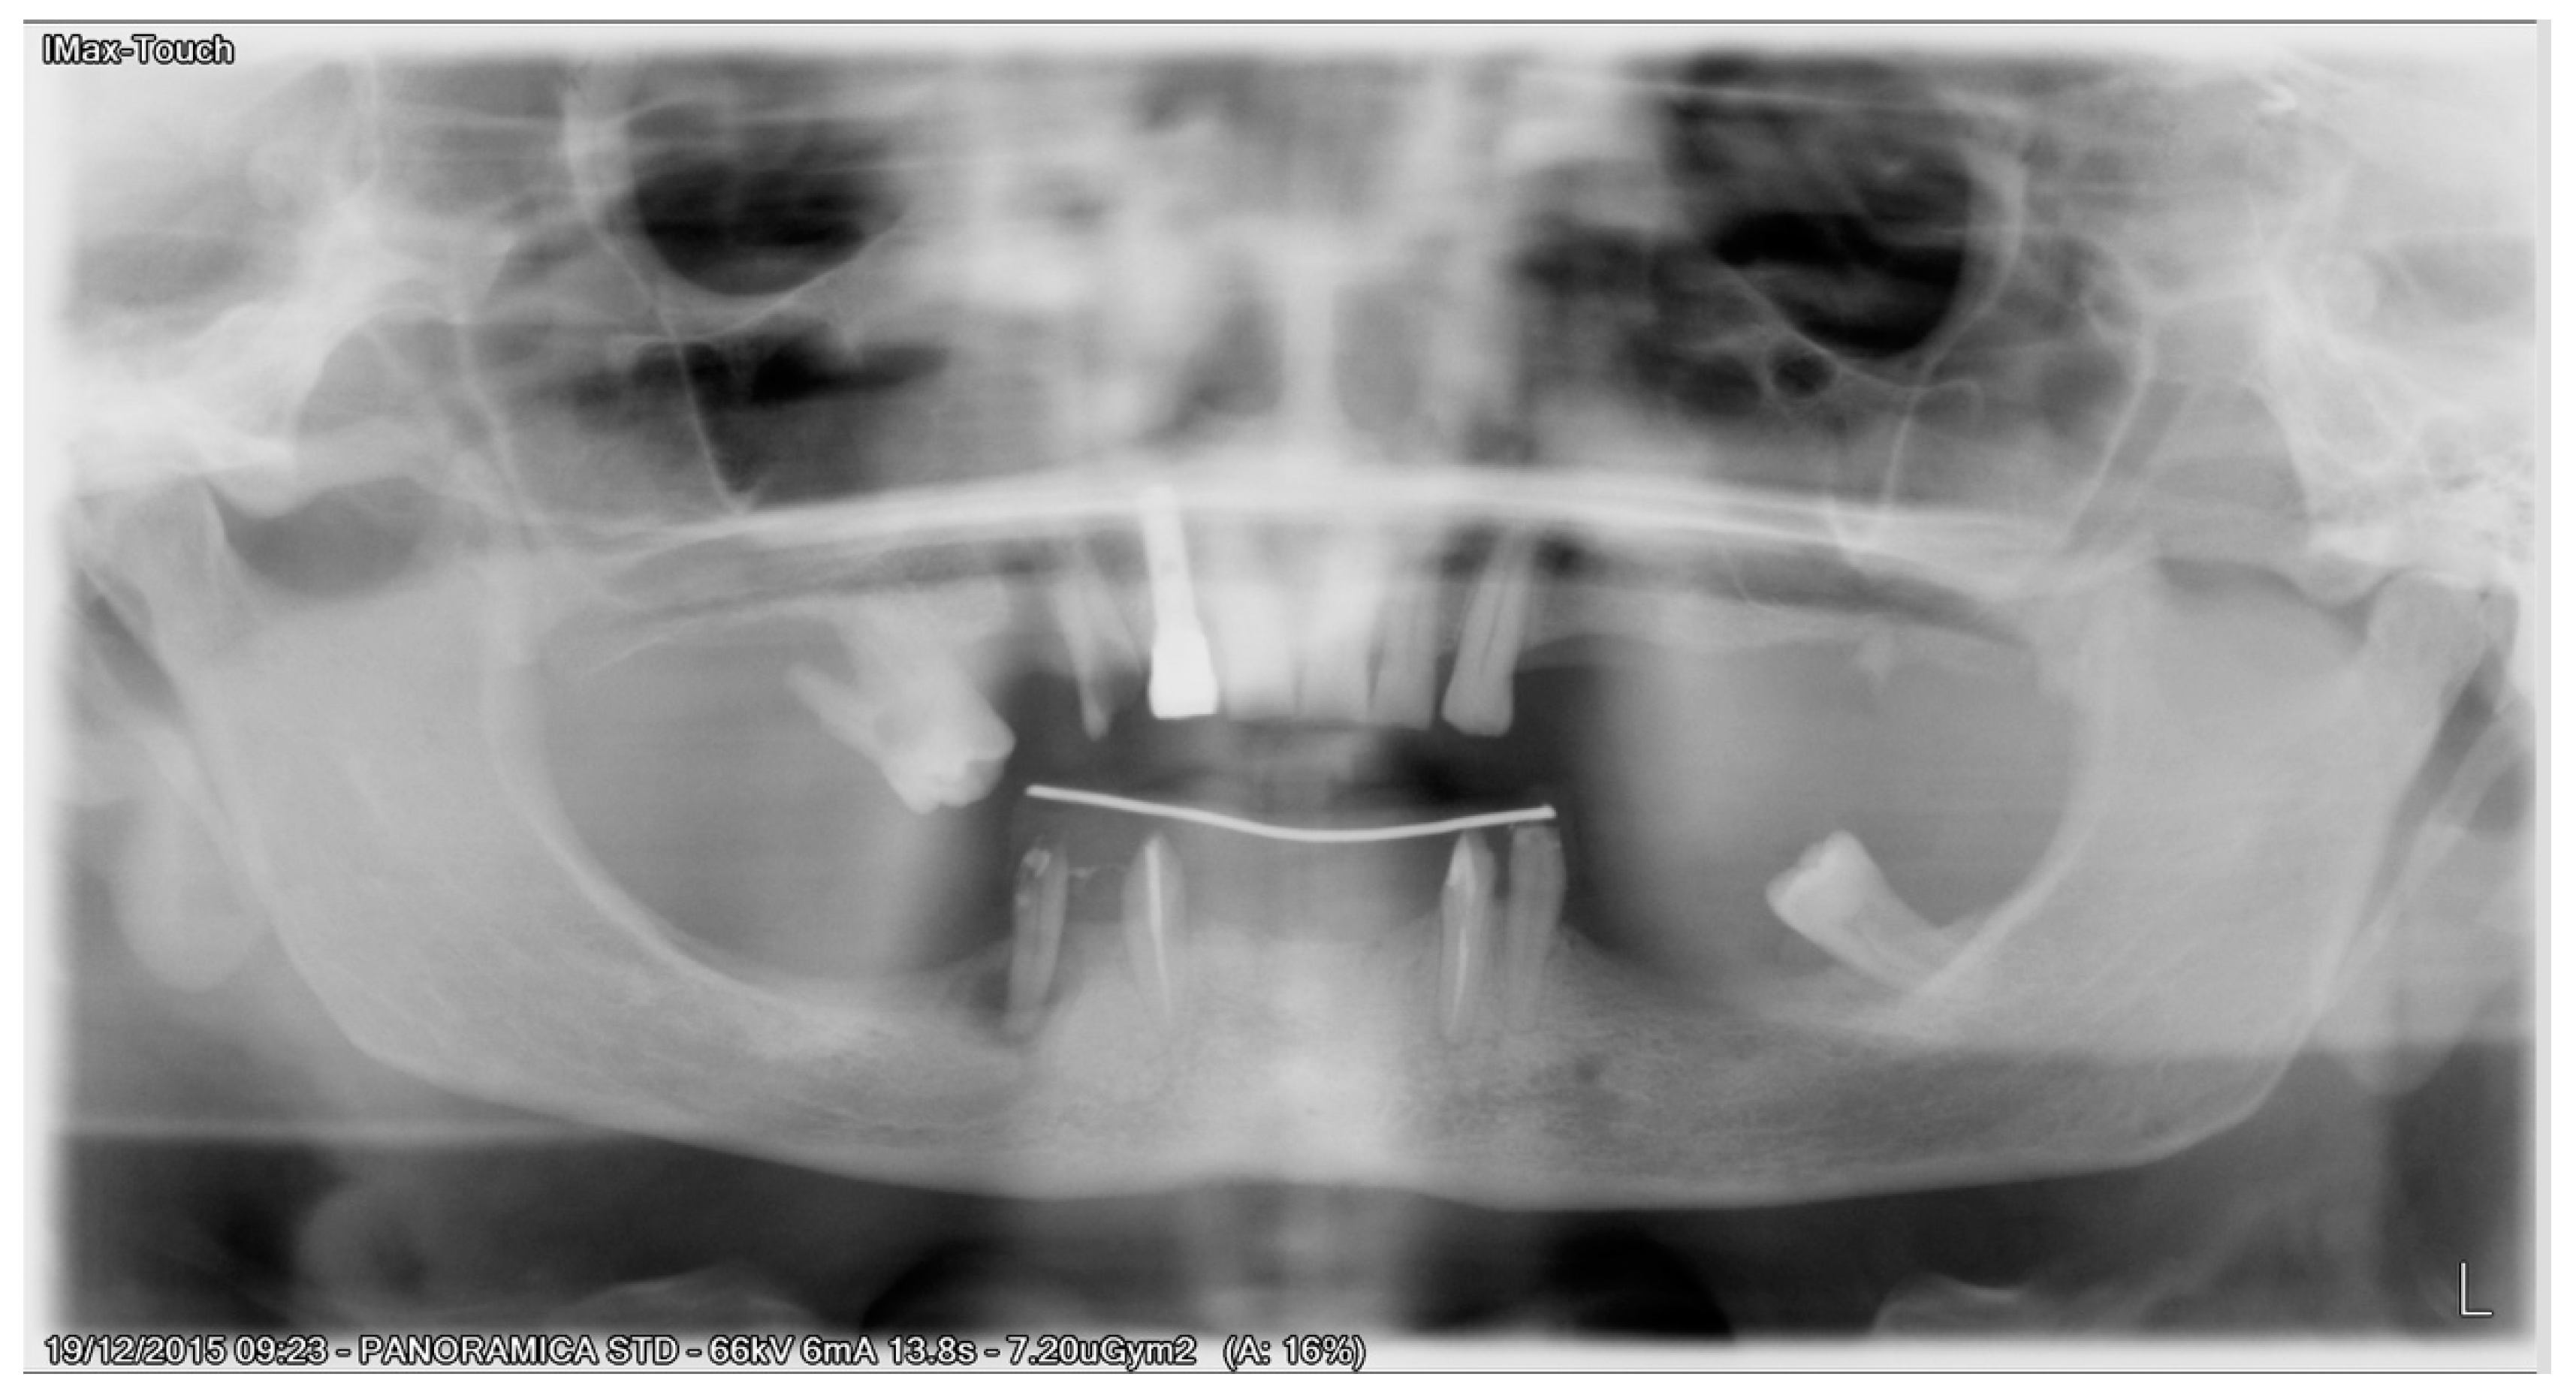

All patients enrolled in this study had panoramic radiographs and/or cone-beam computed tomography (CBCT) (Figure 1).

Figure 1. Preoperative panoramic X-ray.